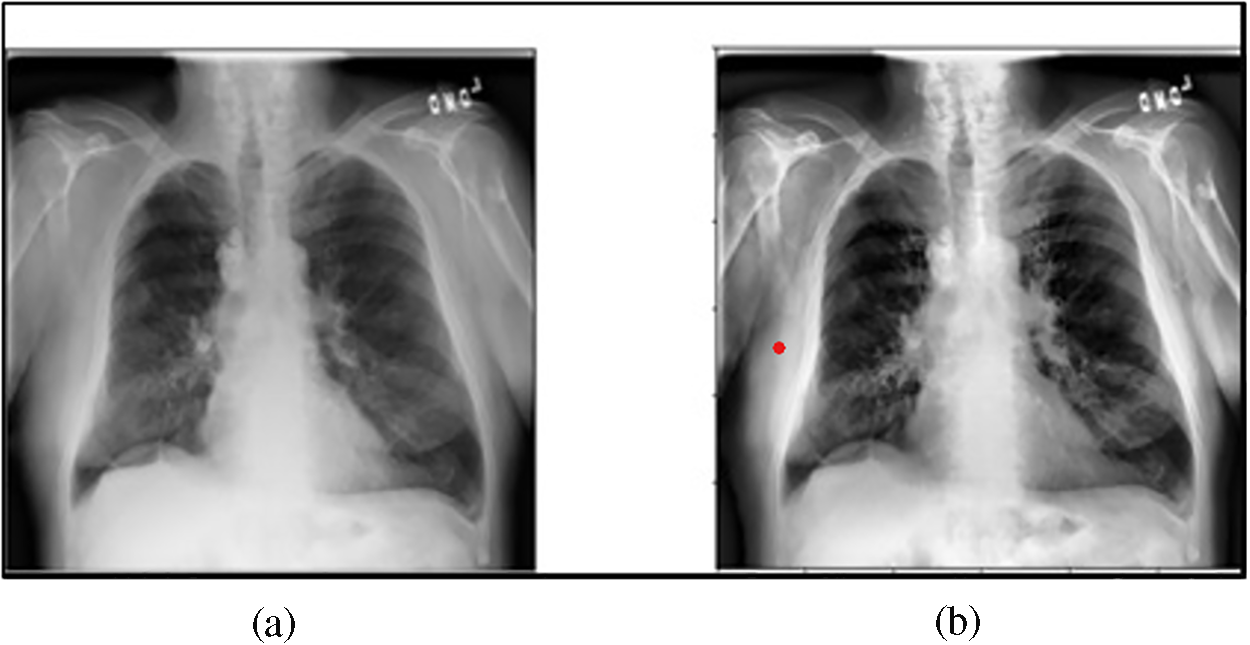

Detecting pulmonary edema and pleural effusion using chest X-rays is crucial for the diagnosis of diseases [1,2]. Pulmonary edema occurs due to fluid buildup in the lungs’ alveoli [3]. Conversely, pleural effusion is a disorder indicated by the abnormal fluid buildup in the membranes surrounding the lungs [4]. Fig. 1a depicts pulmonary edema [5] and Fig. 1b shows pleural effusion [6].

Figure 1: (a) Pulmonary edema (Reprinted from reference [5]); (b) Pleural effusion (Reprinted from reference [6])